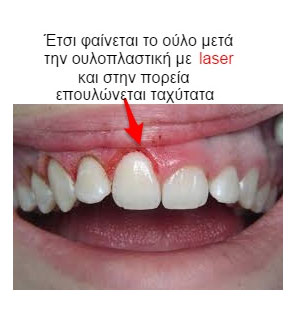

Αν ένας από αυτούς είναι η υπερβολική κάλυψη των δοντιών από ούλα, τότε η διόρθωση είναι εύκολη μια που θα χρησιμοποιήσουμε laser.